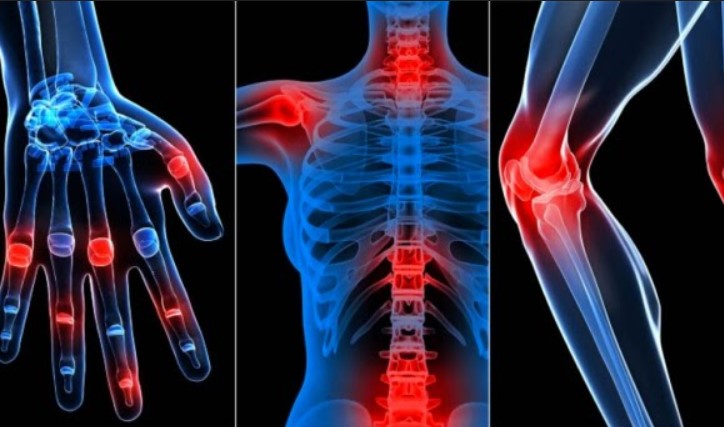

Зубицька: "Секрет - в розумінні причини хвороби. Взагалі в енциклопедіях налічують до 147 можливих причин розвитку остеохондрозу і артрозу, але дослідження знайшли одне - суглоби, хребці і хрящі втрачають свою еластичність, звідси і біль. Вони зношуються через погане кровопостачання.

Зубицька: "Першими ознаками можна вважати, коли у хворого зводить суглоби рук або ніг. Відбувається це найчастіше через фізичне перевантаження суглоба, підняття важких предметів, наприклад важкі сумки, незручне взуття, повторювані рухи – все це веде до перевантаження. Суглобові хрящі руйнуються, кістки починають стикатися одна з одною, тому ви відчуваєте дискомфорт. Внаслідок цього, спочатку з'являється скутість руху і набряклість, а потім кінцівка може повністю віднятися. Також величезну роль грає підвищений вміст солі в організмі. Якщо у вас зводить руки або ноги, вам необхідно терміново обмежити себе в споживанні продуктів і рідини, які містять натрій."